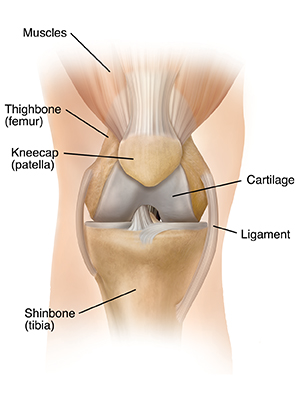

The knee is a joint that works like a hinge. It is formed where the thighbone (femur), shinbone (tibia), and kneecap (patella) meet. It is supported by muscles, tendons, and ligaments. It is also lined with cushioning cartilage. Over time, cartilage can wear away. As it does, the knee becomes stiff and painful. An artificial knee joint (prosthesis) can replace the painful joint and restore movement.

A healthy knee

A healthy knee joint bends easily. Cartilage is a smooth tissue. It covers the ends of the thighbone and shinbone and the underside of the kneecap. Healthy cartilage absorbs stress and allows the bones to glide freely over each other. Joint fluid lubricates the cartilage surfaces, making movement even easier.